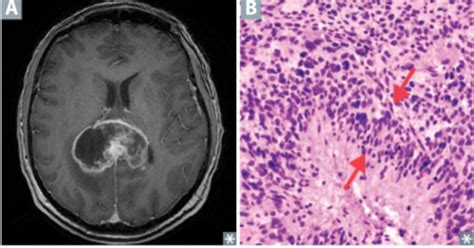

Hey guys! Today we’re diving deep into a term you might encounter when discussing brain tumors: pseudopalisading . It sounds super technical, I know, but understanding it can give you a clearer picture of what’s happening with certain types of brain tumors. So, what exactly is pseudopalisading, and why is it a big deal? Basically, pseudopalisading refers to a specific microscopic pattern observed in brain tumors. When pathologists look at tissue samples under a microscope, they sometimes see tumor cells forming these elongated, crowded rows, almost like they’re lining up along blood vessels or areas of necrosis (dead tissue). It’s like a crowd of people forming a line, but in this case, it’s tumor cells. This pattern isn’t unique to one specific type of brain tumor, but it’s often associated with highly aggressive and fast-growing ones, particularly glioblastoma multiforme (GBM) , which is the most common and deadliest primary brain cancer in adults. The presence of pseudopalisading is a significant indicator for pathologists, suggesting a more ominous prognosis. It hints at the tumor’s aggressive nature, its ability to invade surrounding brain tissue, and its tendency to outsmart treatments. So, while it’s a microscopic finding, its implications are massive for diagnosis, treatment planning, and predicting outcomes. We’ll break down what causes this pattern, why it’s a hallmark of certain aggressive tumors, and how doctors use this information to fight these challenging diseases. Stick around, because this is crucial stuff for anyone navigating the world of brain tumors.

Alright, let’s get a bit more granular and talk about what’s actually happening under that microscope when we see pseudopalisading . Imagine a brain tumor as a bustling, chaotic city. Within this city, there are areas where things are booming and growing rapidly, and other areas where the resources are scarce, leading to the death of cells – these are the areas of necrosis. Pseudopalisading occurs when the tumor cells, in their relentless drive to multiply and spread, start to congregate in the regions surrounding these necrotic zones or along the tiny blood vessels (capillaries) that feed the tumor. It’s like the tumor cells are forming a protective barrier or a staging ground around these critical areas. The ‘pseudo’ part of the word means ‘false,’ and ‘palisading’ refers to a fence-like arrangement. So, ‘pseudopalisading’ means a false fence-like arrangement of tumor cells. They aren’t a true, organized fence, but they look like they are because they are so densely packed and aligned. This unique arrangement is thought to be a response to the harsh microenvironment around the dead tissue. The lack of oxygen and nutrients in the necrotic core might signal to the tumor cells to cluster together, perhaps to share resources, protect themselves, or to prepare for invasion into the healthier, more oxygenated brain tissue nearby. It’s a survival mechanism gone rogue. This pattern is not something you see in benign or slow-growing tumors. It’s a red flag, a siren, screaming ‘aggression!’ The more prominent and extensive the pseudopalisading, generally the more aggressive the tumor is considered to be. This finding is absolutely critical for neuropathologists. When they examine a biopsy, they’re not just identifying that it’s a tumor; they’re grading its severity and predicting its behavior. Pseudopalisading is one of the key features that helps them distinguish between different types of gliomas and guides the subsequent treatment strategy. It’s a visual cue that tells a complex story about the tumor’s biology and its potential to cause harm. So, while it might sound like a minor detail, this microscopic pattern is a cornerstone in the diagnosis and management of aggressive brain cancers.

Now, let’s talk about the star player, or rather, the villain, often associated with pseudopalisading : glioblastoma multiforme (GBM) . Guys, if you hear about pseudopalisading in the context of a brain tumor, GBM is very likely on the table. This is because pseudopalisading is considered one of the hallmark histological features of glioblastoma. What does that mean? It means it’s one of the defining characteristics that pathologists look for when diagnosing GBM. GBM is the most common type of malignant glioma, meaning it’s a primary brain cancer that arises from glial cells (the supportive cells of the brain), and it’s notoriously aggressive. Its hallmark is its rapid growth and its tendency to infiltrate extensively into the surrounding normal brain tissue, making it incredibly difficult to remove completely through surgery. The presence of pseudopalisading in a GBM biopsy is like a flashing neon sign indicating just how aggressive this tumor is. The dense lining up of tumor cells around areas of necrosis and microvascular proliferation (another key GBM feature, where new, abnormal blood vessels form) is a direct visual representation of the tumor’s relentless march. It suggests that the tumor cells are actively responding to their environment, adapting, and seeking out new territory. Think of it as the tumor’s way of regrouping and strategizing its attack. The cells forming the palisades are often in a state of high proliferation, meaning they’re dividing rapidly. This characteristic pattern helps pathologists differentiate GBM from less aggressive gliomas, such as diffuse astrocytomas or oligodendrogliomas, where these features are typically absent or much less pronounced. The implication of finding pseudopalisading in a GBM is significant. It reinforces the understanding that this is a tumor that needs to be treated aggressively and with a multi-modal approach. It tells the medical team that the tumor is likely to recur, even after treatment, and that close monitoring will be essential. So, when you hear about pseudopalisading, it’s almost always in conjunction with the most challenging form of brain cancer, underscoring the severity and the urgent need for effective therapeutic strategies. It’s a critical piece of the puzzle in understanding and fighting glioblastoma.